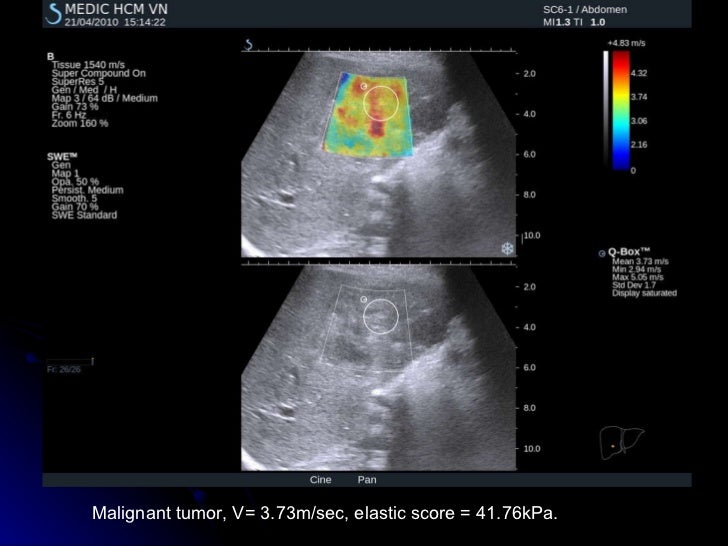

From www.slideshare.net

SHEAR WAVE ELASTOGRAPHY of LIVER TUMORS What Is Shear Wave Elastography Liver The speed of the shear wave can be measured in a small. Strain elastography (se) and shear wave elastography. Ultrasound elastography, or the estimation of tissue stiffness by ultrasound, refers to a group of technologies that estimate tissue stiffness,. Shear wave elastography (swe) assesses the biomechanical properties of the liver tissue giving a numerical value of stiffness that. In soft. What Is Shear Wave Elastography Liver.